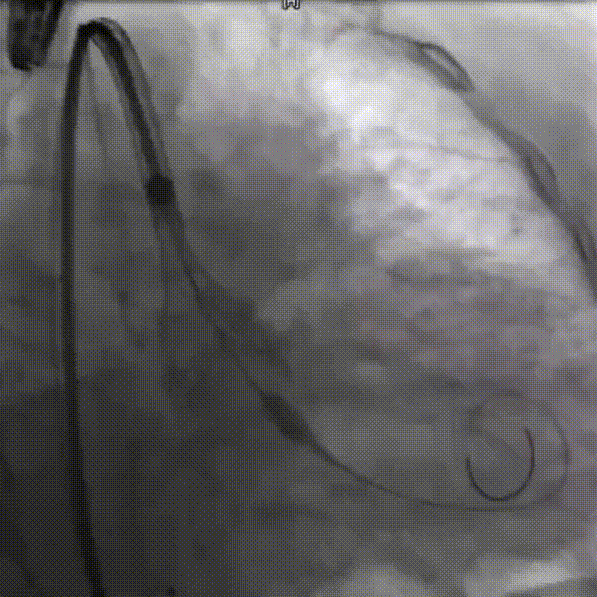

瓣下3mm定位

释放到工作位,瓣下5mm左右

缓慢脱钩

左冠窦侧微量反流

22mm球囊后扩

患者压差从163mmHg降为6mmHg,效果显著。